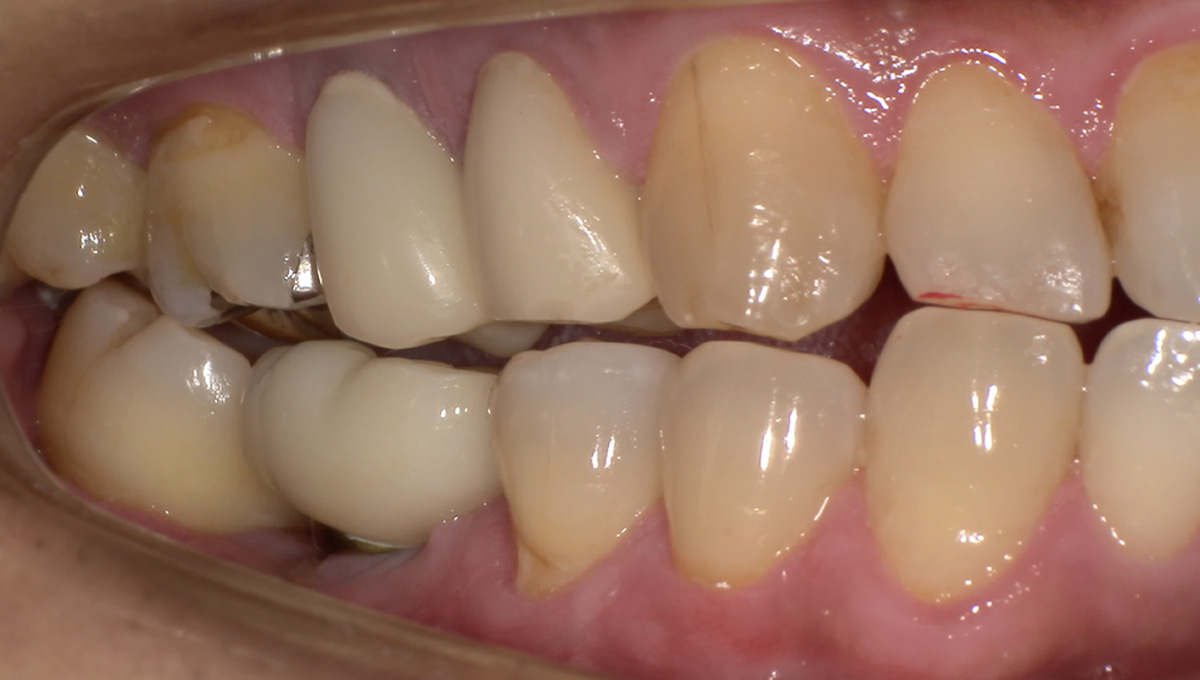

親抜歯後、歯ぐきは治癒しました。しかし、インプラント治療のためには骨が不足していました。

CT画像 -